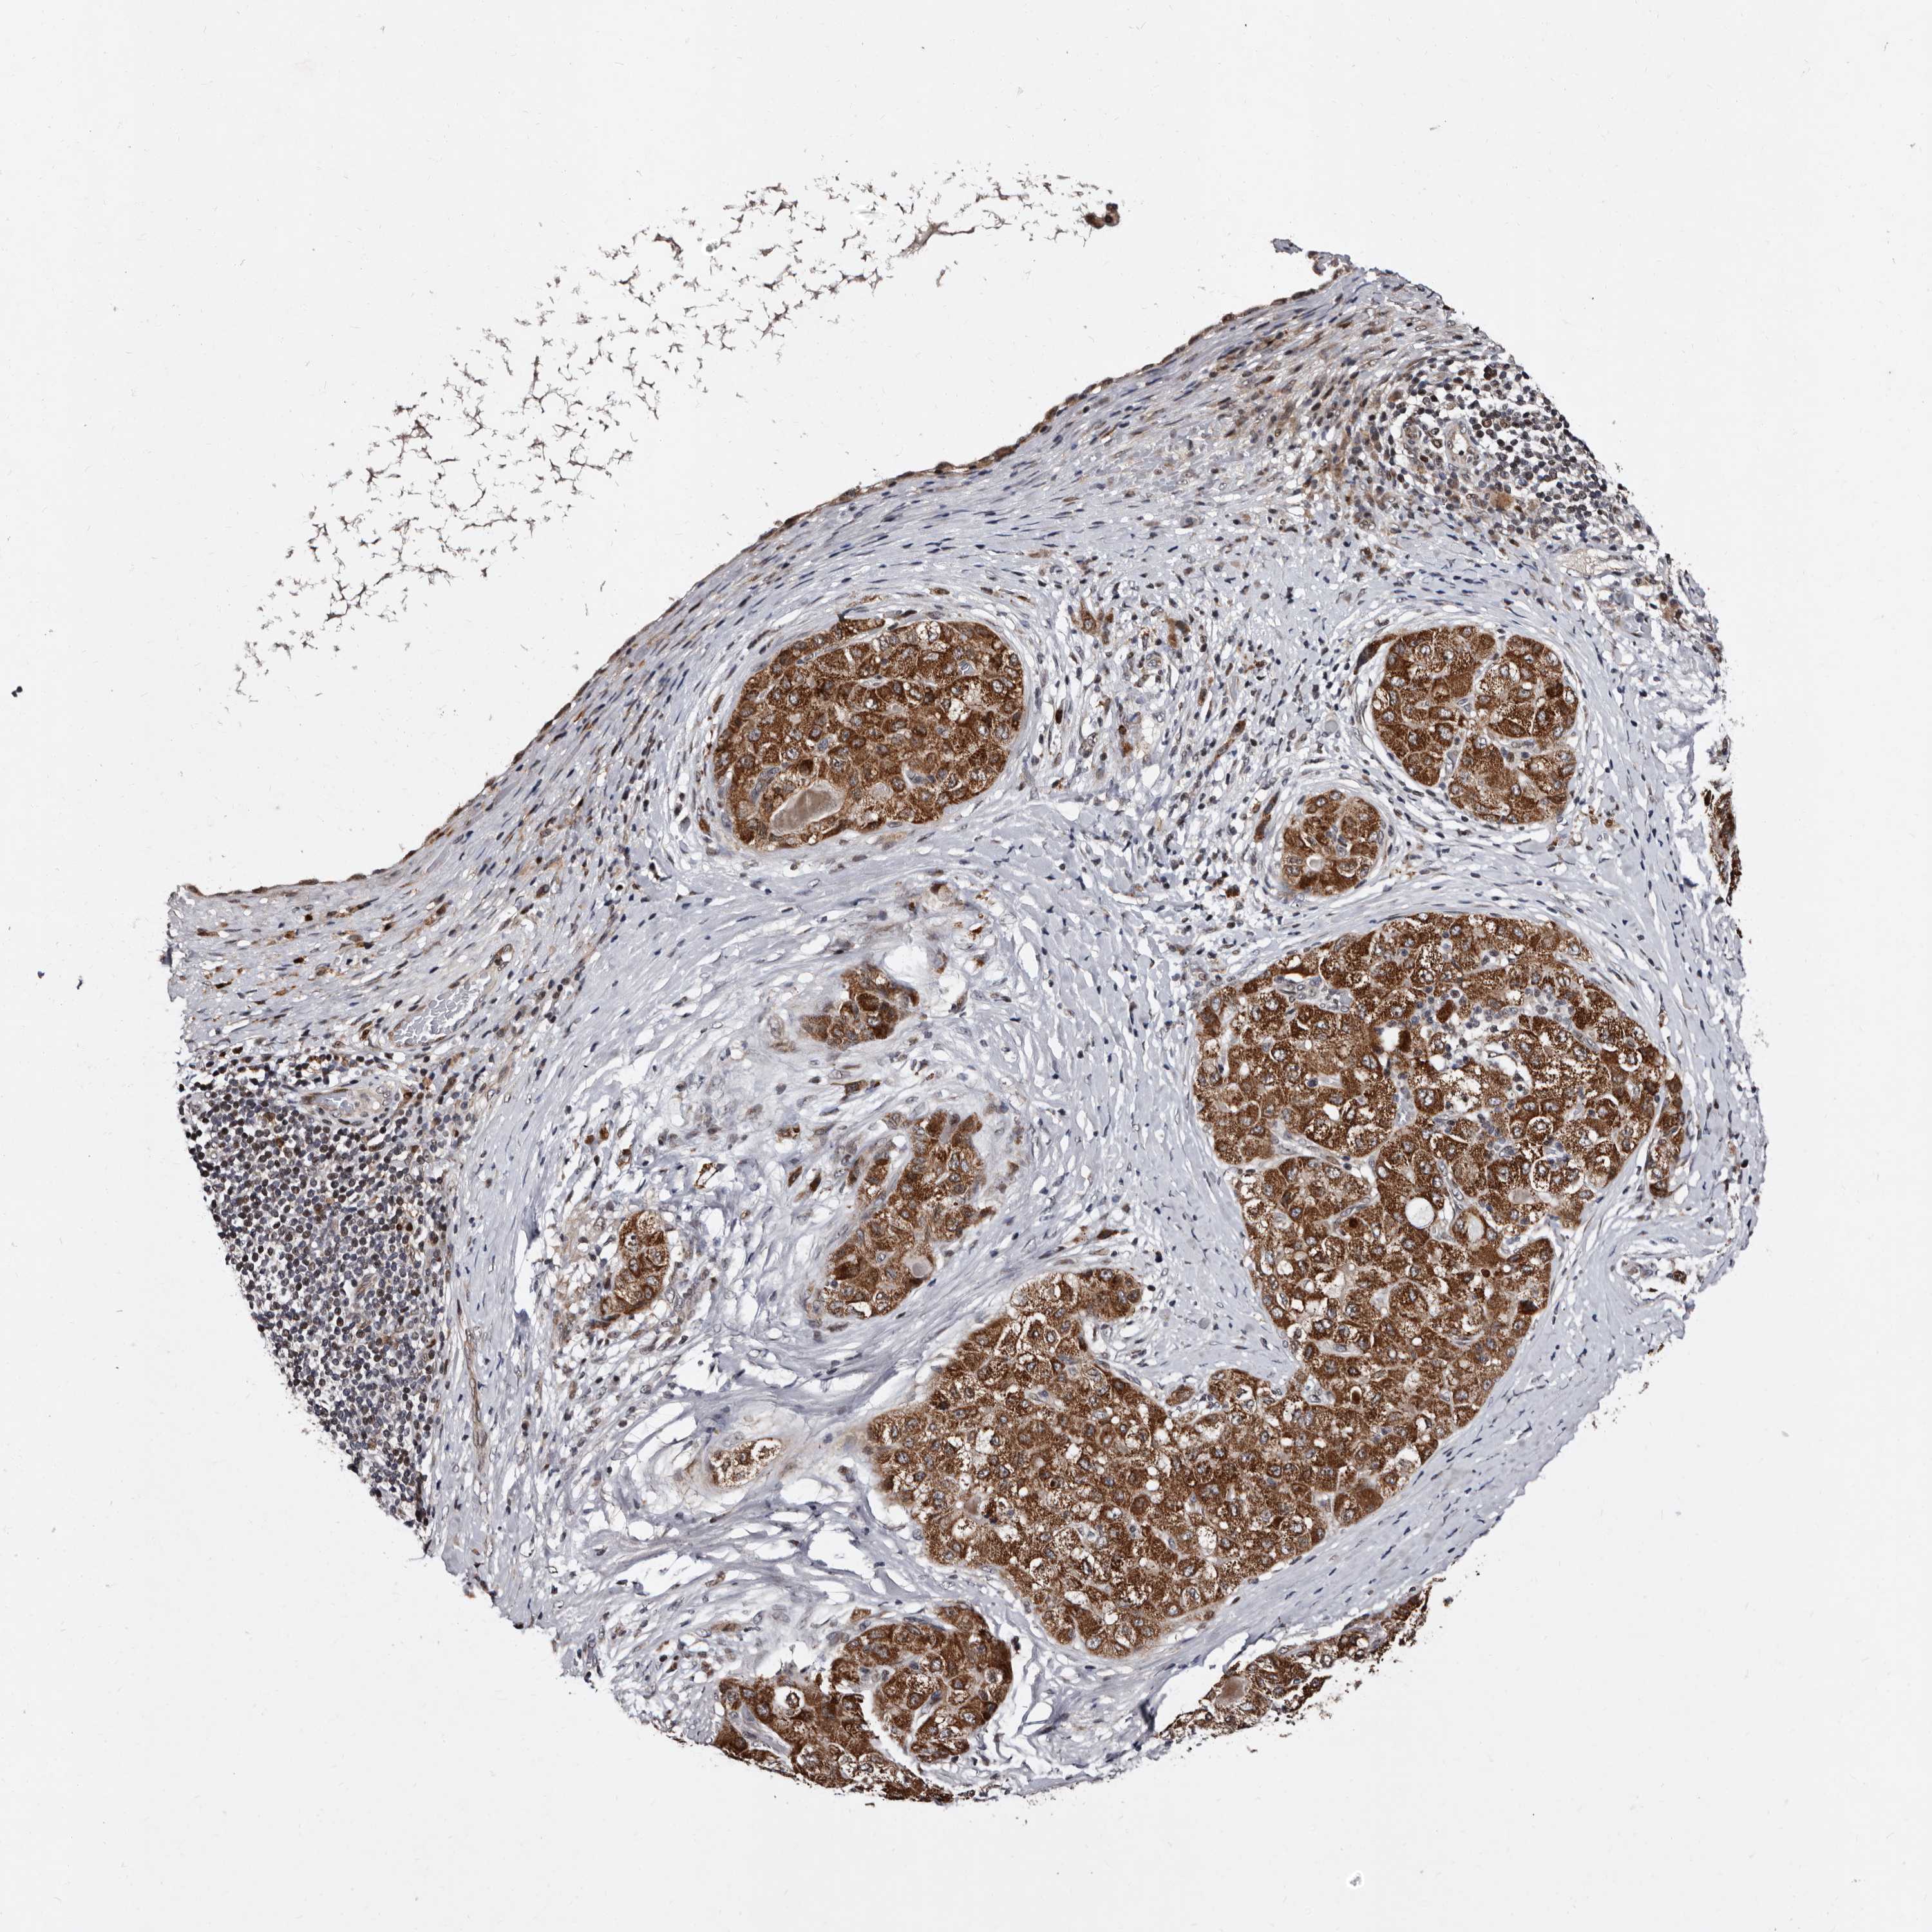

LIVER CANCER - Protein expressioni

A mouse-over function shows sample information and annotation data. Click on an image to view it in a full screen mode. Samples can be filtered based on level of antibody staining by selecting one or several of the following categories: high, medium, low and not detected. The assay and annotation is described here.

Note that samples used for immunohistochemistry by the Human Protein Atlas do not correspond to samples in the TCGA dataset.

Antibody stainingi

Antibody staining in the annotated cell types in the current human tissue is reported as not detected, low, medium, or high, based on conventional immunohistochemistry profiling in selected tissues. This score is based on the combination of the staining intensity and fraction of stained cells.

Each image is clickable and will lead to virtual microscopy that enables deeper exploration of all samples and also displays staining intensity scores, fraction scores and subcellular localization as well as patient and tissue information for each sample.

Antibody HPA025690

Staining

High

Medium

Low

Not detected

Intensity

Strong

Moderate

Weak

Negative

Quantity

>75%

75%-25%

<25%

None

Location

Nuclear

Cytoplasmic/membranous

Cytoplasmic/membranous,nuclear

Cholangiocarcinoma

Carcinoma, Hepatocellular, NOS